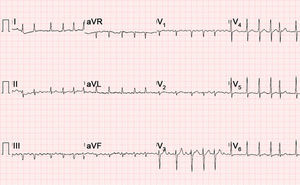

A 70-year-old man presented to the emergency department of our hospital with acute heart failure in the context of atrial fibrillation with rapid ventricular response (Figure 1). Physical examination revealed an irregular pulse, with moist rales in lung fields and lower extremity edema. In addition, a simultaneous electrocardiographic recording disclosed the absence of heart sounds during short diastoles. This finding of “silent” heartbeats led us to perform an echocardiogram, which revealed a left ventricular ejection fraction dependent on the R-R interval, which was normal during long diastoles and showed severe systolic dysfunction during short diastoles. M-mode recording of the mitral and aortic valves was carried out to acquire short-axis images from the parasternal window; they disclosed the failure of the mitral valve to open during short R-R intervals (Figure 2, arrow), as well as the failure of the aortic valve to open during the beat that followed (Figure 3, arrows).